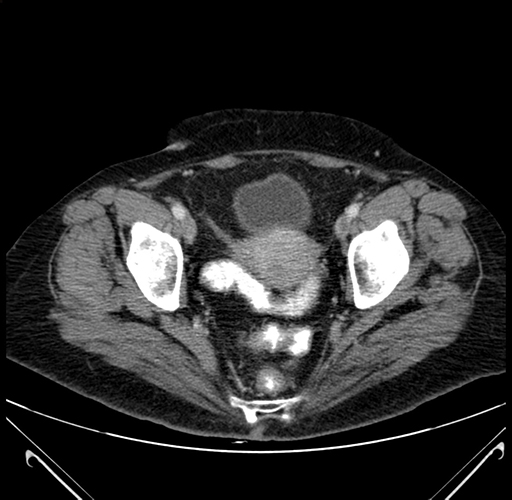

Coronal Venous